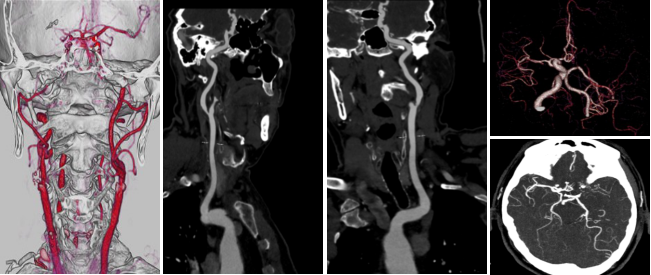

病例二 男,69歲, 于1月前無(wú)明顯誘因出現(xiàn)右上肢麻木不適, 此癥狀間斷存在, 持續(xù)數(shù)分鐘, 活 動(dòng)后好轉(zhuǎn)。 于1周前上述癥狀持續(xù)存在, 活動(dòng)后未見(jiàn)好轉(zhuǎn)入院檢查。

根據(jù)左側(cè)頸內(nèi)動(dòng)脈閉塞的長(zhǎng)度、形態(tài)以及側(cè)枝循環(huán)代償情況,考慮左側(cè)頸內(nèi)動(dòng)脈為慢性閉塞。

腦血流灌注圖可見(jiàn)CBF輕微下降,CBV略升高,MTT升高 ,TTP升高明顯。

640層寬體探測(cè)器CT灌注聯(lián)合CTA檢查,可在CTA掃描發(fā)現(xiàn)血管異常時(shí), 應(yīng)用CTP協(xié)助發(fā)現(xiàn)異常灌注區(qū), 對(duì)缺血的程度及代償情況進(jìn)行評(píng)估; 對(duì)照多時(shí)相血管CTA,找到責(zé)任血管, 評(píng) 價(jià)側(cè)支循環(huán); 兩者從形態(tài)學(xué)及功能學(xué)多方面對(duì)缺血性腦病進(jìn)行評(píng)估, 對(duì)臨床個(gè)性化診斷和治療具有重要指導(dǎo)意義。